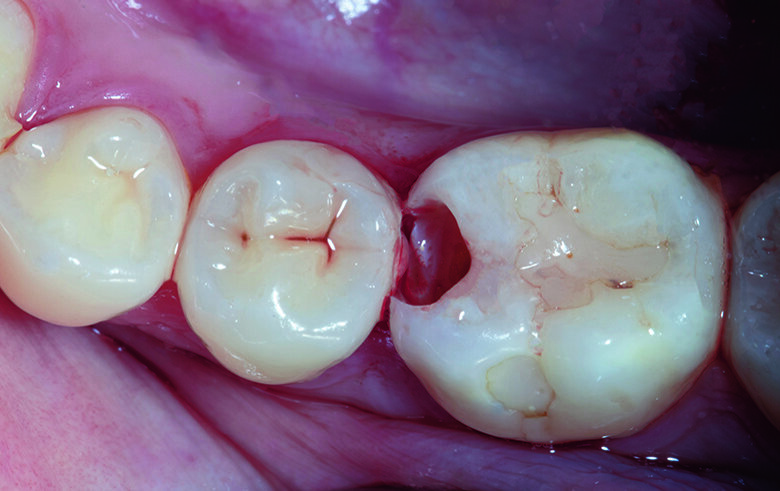

A 21-year-old female visited the dental office with a chief complaint of food lodgment and pain in tooth #46 when consuming sweet or cold food. Radiographic examination with IOPA reveled old composite restoration in tooth #46 and distal decay on #45 without involving the marginal ridge. Upon clinical examination, Class II cavities on tooth #46 & #45 were identified (Fig. 1). The most suitable treatment approach in this situation was direct restorations with bioactive composite resins.

Fig. 1. MO Class II cavity along with old composite restoration on tooth #46 and distal decay on tooth #45.